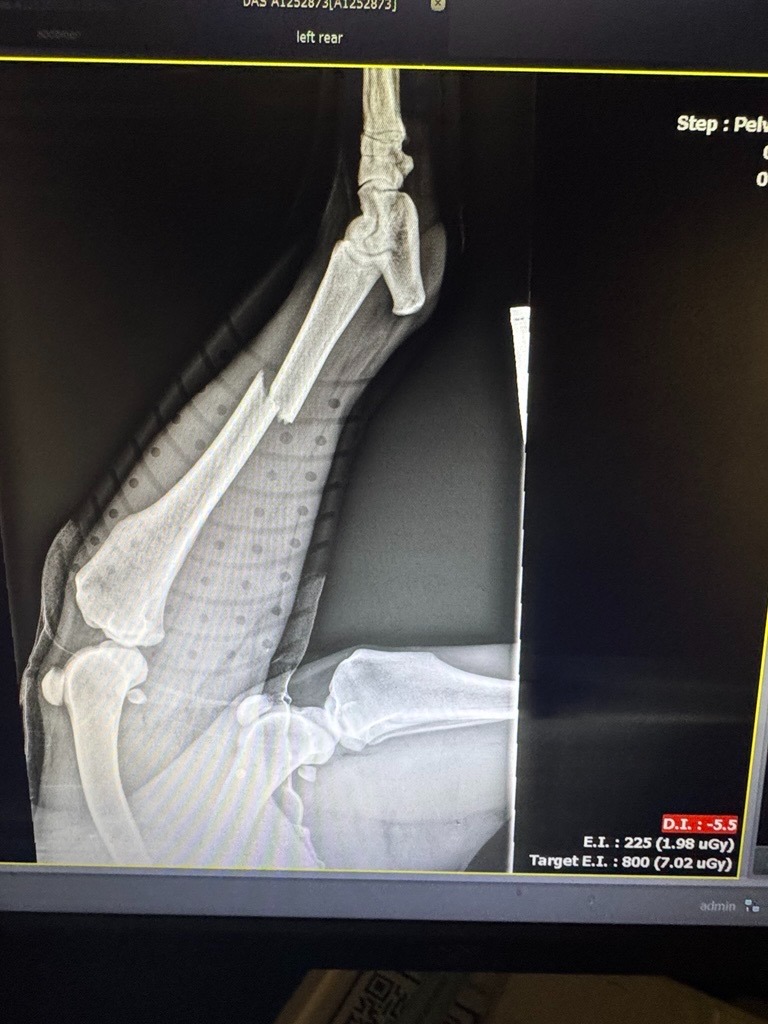

Meet Queen my new foster. She is a 70 pound, 3-year-old stray great Pyrenees from Dallas, TX. She was found after being hit by a car with puncture wounds from a dog attack and a pretty bad fracture. I am not rich. I am a mother of two boys and a pet parent. But I can't let this dog be euthanized and Dallas animal services can only do so much. This dog either needs surgery or will lose her leg. Please help me afford the veterinary cost of saving her leg or if it is in her best interest, having it amputated. I will give her a home and somewhere safe with food and other dogs to love on. I know this dog is meant for someone and it is a miracle from God that she is alive. I intend to help her get to the next place and her forever family but I need help from my community to do this.